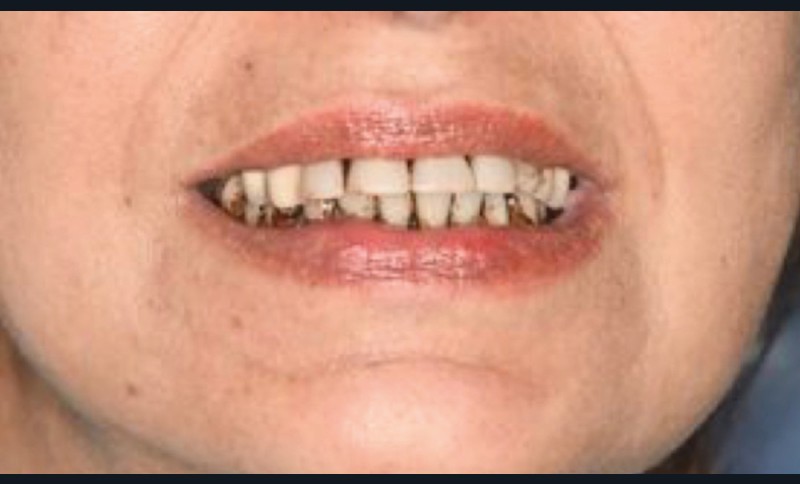

Un trismus peut accompagner les douleurs, ainsi qu’une tuméfaction génienne basse intéressant la branche horizontale et l’angle mandibulaire, avec voussure vestibulaire. L’absence de fistule gingivale, d’adénopathies cervicales et de paresthésies labio-mentonnières fait évoquer ce diagnostic. Parfois, une biopsie peut être pratiquée.